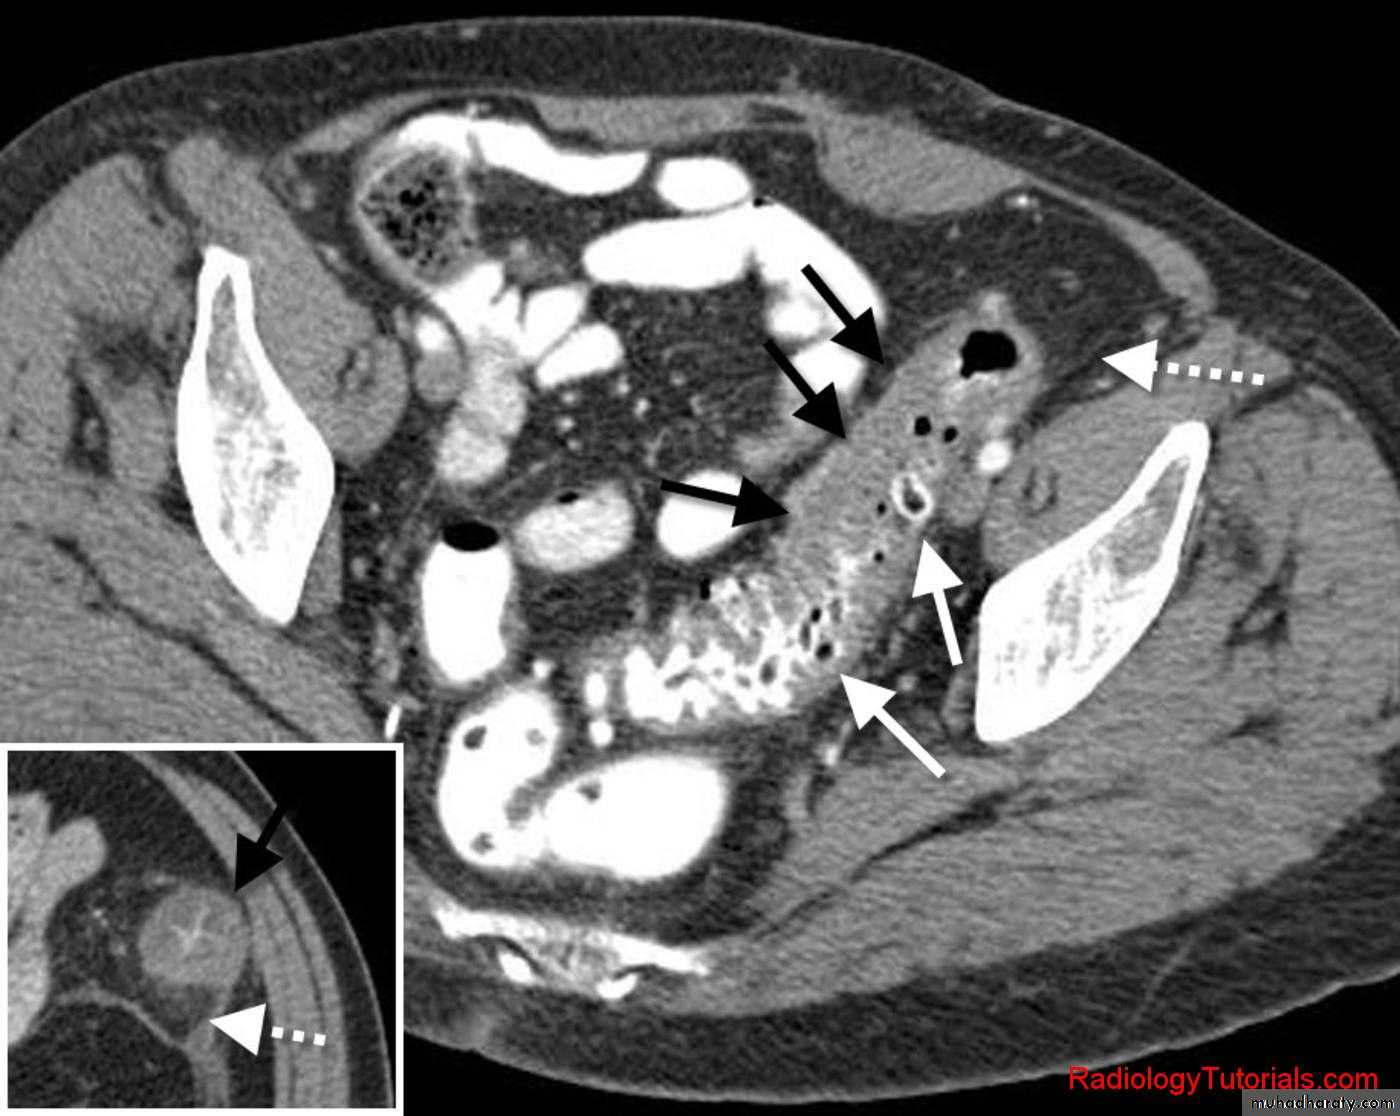

• CT signs of urinary tract obstruction:

• Dilatation of the ureter above the calculus• Dilatation of renal pelvis and collecting system

• Soft tissue stranding in the perinephritic fat due to distended lymphatic channels.

A major advantage of CT is that non-renal causes of acute flank pain may also be diagnosed